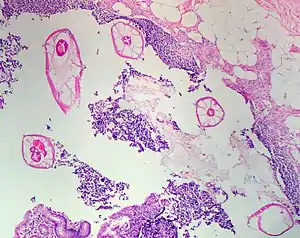

![]() Гострики в апендиксі Гострики в апендиксі | |

В основі патогенного впливу гостриків на організм людини лежить механічна дія гельмінтів на слизову оболонку кишечника, пов'язана з подразненням механорецепторів і хеморецепторів при їх фіксації та руху. Подразнення ілеоцекальної ділянки призводить до можливості розвитку ентероколіту. При проникненні в червоподібний відросток гострики можуть стати причиною апендициту.